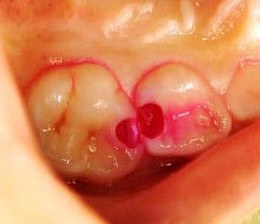

「う蝕検知液」で、虫歯だけを検出

当院では、治療の指針として「う蝕検知液」という特殊な検査薬を使用しています。

この検査薬は、虫歯菌に侵された組織だけに反応して着色する性質を持っています。

色がつくことでハッキリと視覚化されるので、取り残しを徹底的に防ぎ、削りすぎを回避できます。